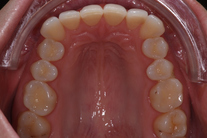

32-årig kvinna som tycker att hon bara visar sina framtänder. En utjämning och vidgning av tandbågen med 8 månaders genomskinliga Invisalignskenor, gav henne ett fint leende.